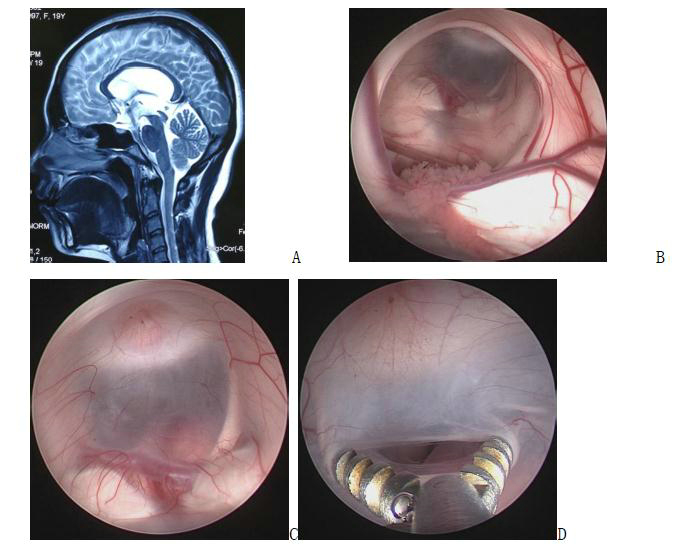

图4. A、B手术前增强磁共振;C 手术中截图,提示肿瘤全部切除,可以看到垂体柄、视交叉和大脑前动脉;D、E内镜经鼻手术后磁共振,提示肿瘤全切。